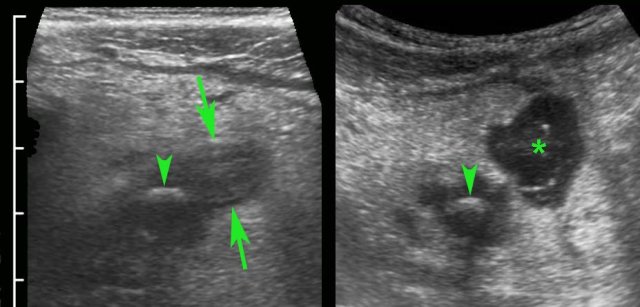

Two asymptomatic individuals with large, feces-filled but non-inflamed appendices demonstrated by US and CT scan.

Note complete absence of inflamed fat in both.